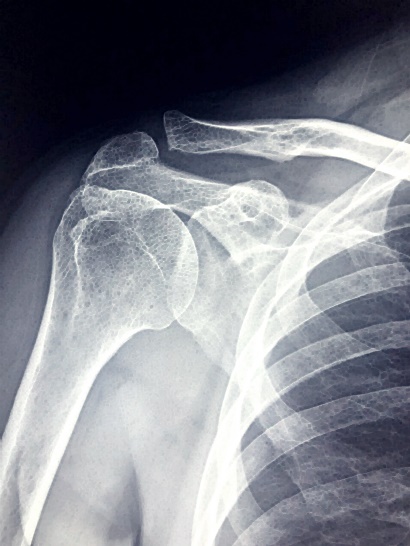

✅ 어깨 관절염

시간이 지남에 따라 어깨 관절의 연골이 마모되어 통증을 유발할 수 있습니다. 이는 주로 노화 과정에서 나타납니다.

1. 노화: 가장 일반적인 원인으로, 나이가 들면서 관절 연골이 자연스럽게 마모됩니다.

2. 외상 후 관절염: 어깨 부상이나 골절 후에 발생할 수 있으며, 과거의 부상이 관절염으로 이어질 수 있습니다.

3. 류마티스 관절염: 자가면역 질환으로, 몸이 자신의 조직을 공격하여 염증과 통증을 유발합니다.

4. 유전적 요인: 가족력이 있는 경우, 어깨 관절염의 위험이 높아질 수 있습니다.